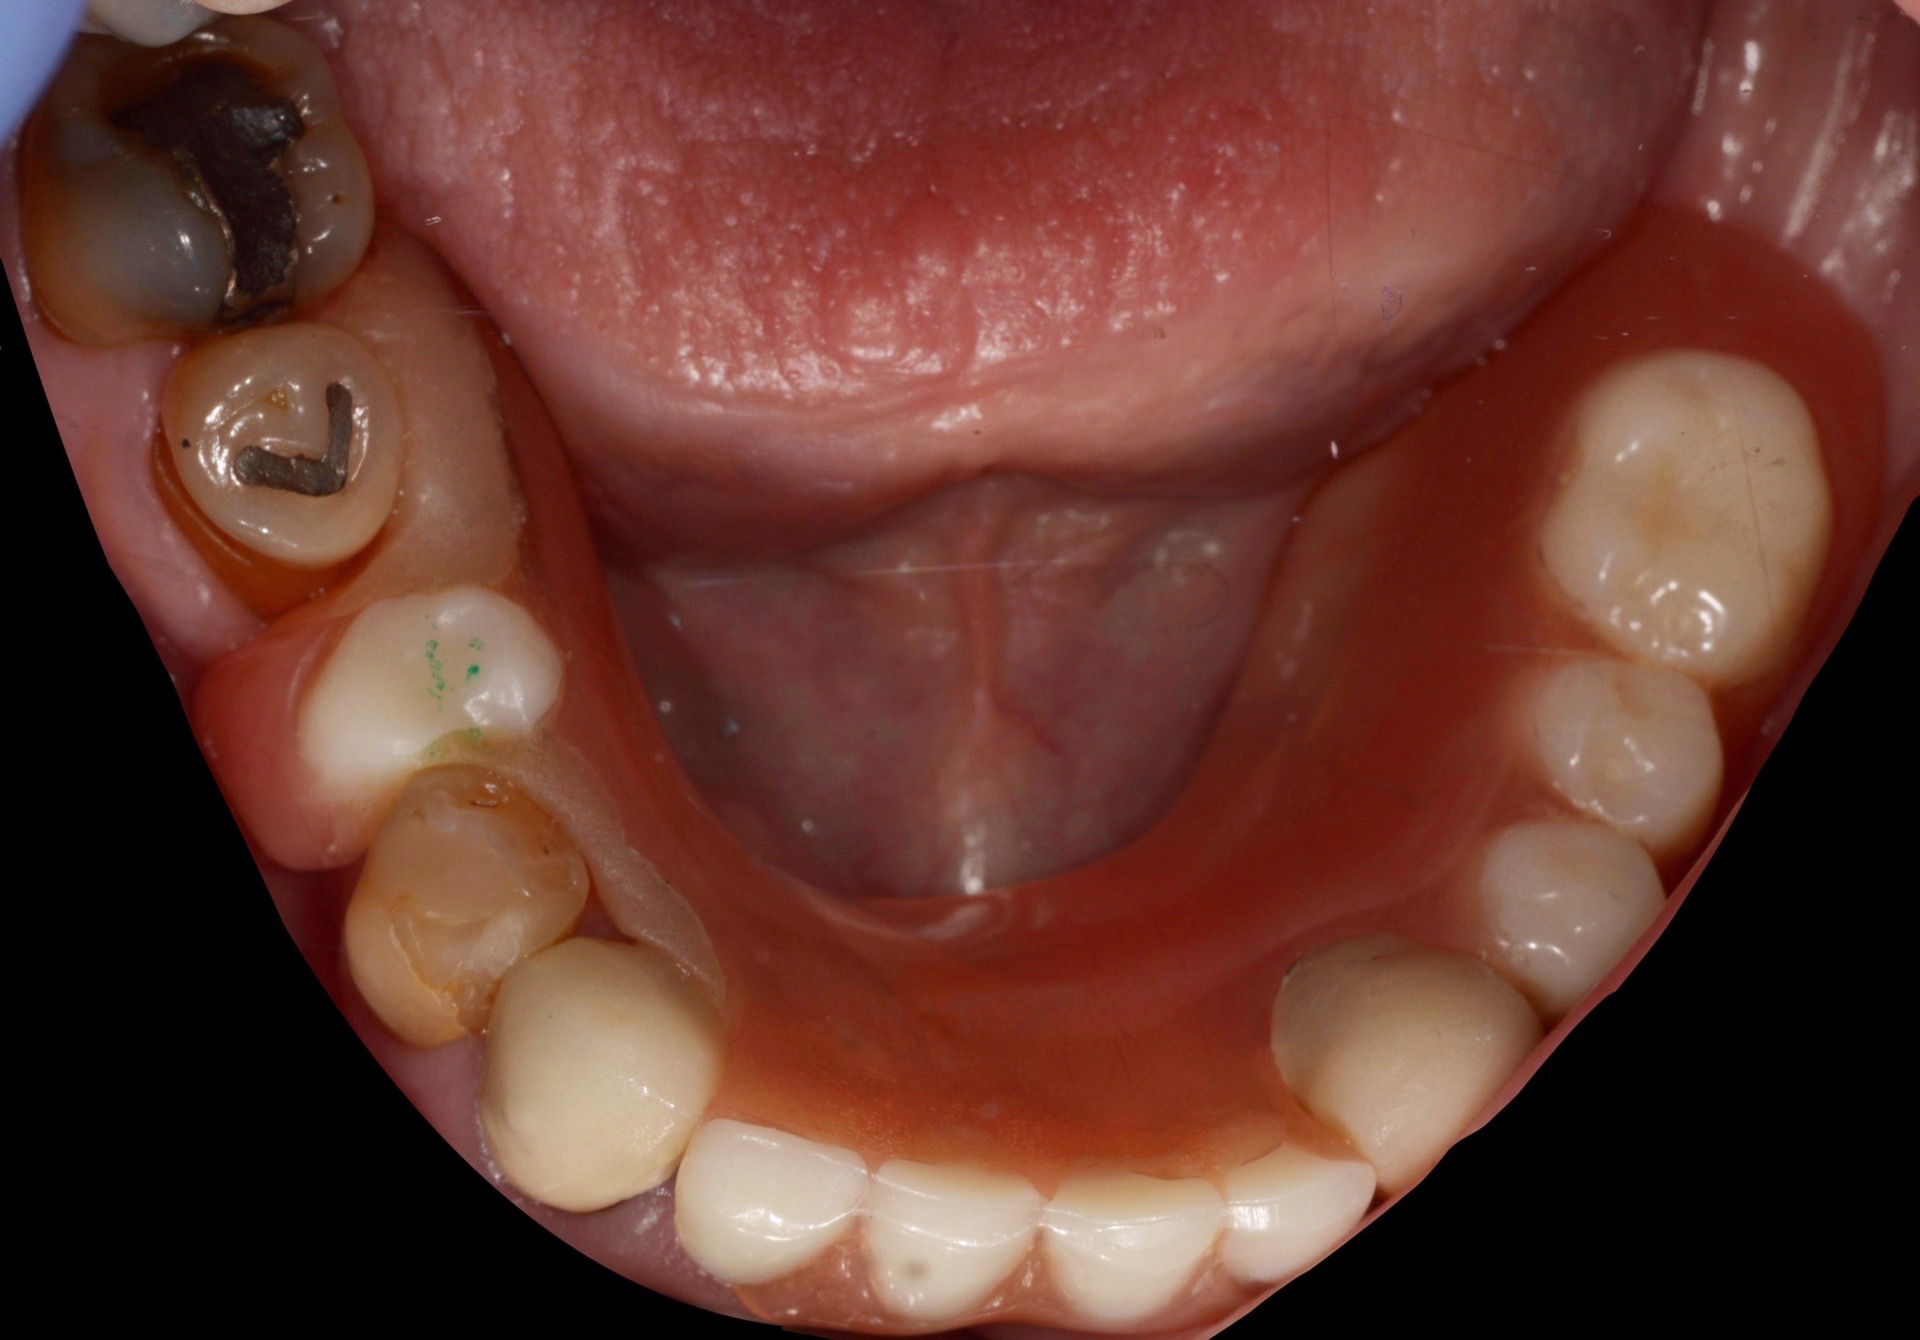

Στην κάτω γνάθο, τα υπάρχοντα δόντια δέχτηκαν στεφάνες, ενώ παράλληλα, τοποθετήθηκε ένα εμφύτευμα για την βελτίωση της συγκράτησης της νέας μερικής οδοντοστοιχίας που κατασκευάστηκε.